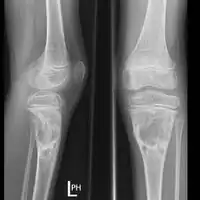

X-ray and CT scan show lytic expansion lesions with clear borders.[1] Expansion of cortex gives the lesion a balloon-like appearance. Larger lesions may appear septated.[10] MRI reveals fluid levels.[1] Bone scan shows outer radiotracer uptake, with a central dark area.[1]

-

X-ray: ABC large long bone of lower leg near knee -